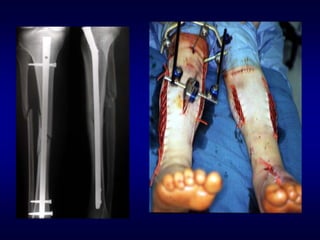

Treating the fracture

• How are we going to hold the reduction?

– Semi-rigid (Plaster)

– Rigid (Internal fixation)

Indications for operative treatment

• General trend toward operative treatment last

30 yrs

– Improved implants and antibiotic prophylaxis, use

of closed and minimally invasive methods

• Current absolute indications:

– Polytrauma, displaced intra-articular fractures

– Open #’s, #’s with vascular injury or compartment

syndrome

– Pathological #’s, Non-unions